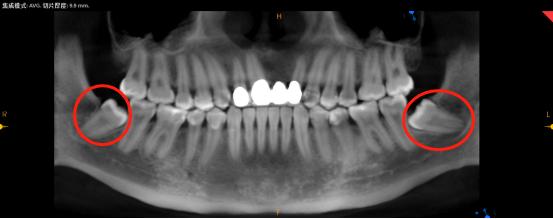

我们通常所讲的会造成严重后果的智齿,都是指下颌智齿。那么可能引起严重后果的下颌智齿又有哪些情况呢?如下图:

近中阻生

水平埋伏阻生

如果我们不把上图情况的智齿拔掉,最直接的影响就是智齿旁边的牙可能会被顶坏,导致牙髓发炎需要根管治疗,甚至牙根都可能烂掉,最终无法保留,只能拔除。